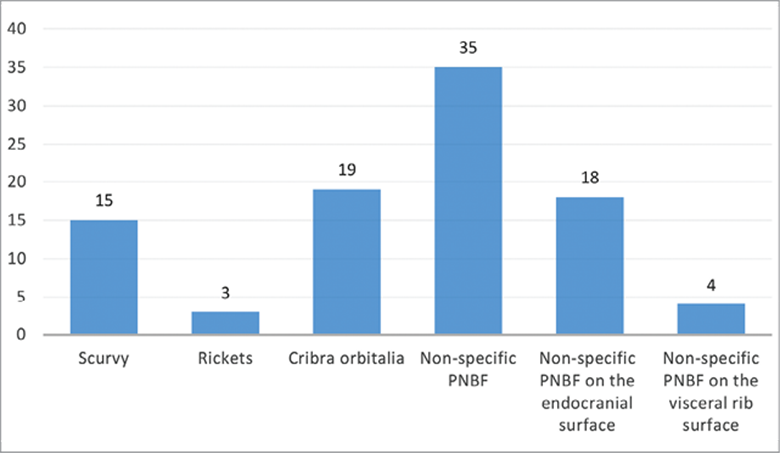

The results of the paleopathological examination are presented for non-adults and adults in Fig. 5. Crude prevalence rates (CPR) of pathology in non-adults (in %).

5 pav. Patologijų pasiskirstymas (%) nesuaugusiųjų grupėje. and Fig. 7, respectively. A total of 113 individuals (74.8% of the total sample) had at least one pathological condition. Non-adults demonstrated more pathological cases than adults – in total 48 cases (42.5% of total pathological cases), including non-specific stress markers and metabolic bone disorders (Fig. 5).

Fig. 5. Crude prevalence rates (CPR) of pathology in non-adults (in %).

5 pav. Patologijų pasiskirstymas (%) nesuaugusiųjų grupėje.

Within non-adults, the highest prevalence rate was the PNBF (24 cases or 35%). The rates of scurvy (10 cases or 15%), cribra orbitalia (13 cases or 19%) and PNBF on the endocranial surface (12 cases or 18%) were also exceptionally high. The lowest rates, counting for only 3%–4% (2 and 3 cases respectively), in the non-adult group were for rickets (Fig. 6. Grave No. 92, non-adult, 2–4 years old. A case of rickets. Note the slight bowing of both tibiae. Photo courtesy Rūta Brindzaitė.

6 pav. Kapas Nr. 92, nesuaugęs individas, 2–4 metų. Rachito atvejis, kuriam būdingas abiejų blauzdikaulių išlinkimas. Rūtos Brindzaitės nuotrauka) and non-specific PNBF on the visceral rib surfaces. Overall, the prevalence of pathology was high in all non-adult age groups, with more than one condition recurring in a non-adult individual.